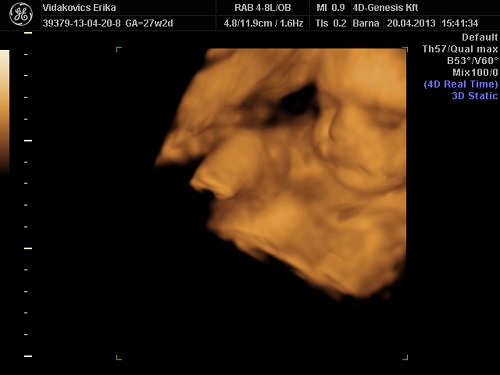

Voltam megint uh-n, nagyon nagy élmény volt, imádom! Dokihoz majd június elején megyek, nagyon kiváncsi vagyok a méhszáj állapotára, mert rengeteget keményedik a hasam. Pihenni meg ... Nem tehetek róla, nekem nem megy a pihenés!